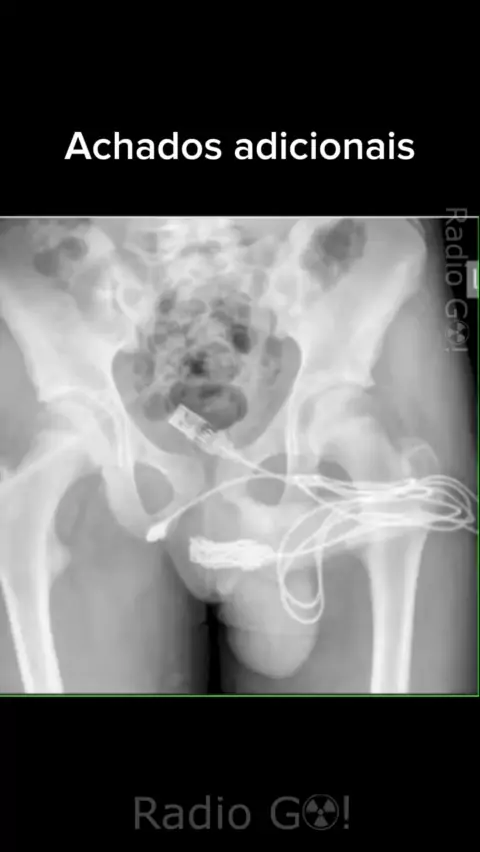

#radiologia #rx #radiodiagnostic #meme #radiologiameme